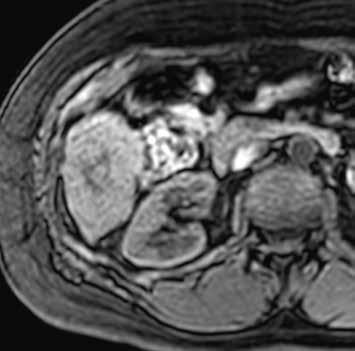

U pacientů s velkými regenerativními uzly vidíme hypervaskularizované ložisko či ložiska, jejichž sycení přetrvává i do portální fáze vyšetření (obr. 13–19). V nativním MR obraze jsou patrná ložiska – v T1-váženém obraze hyperintenzní a v T2-váženém obraze izointenzní či heterogenně intenzní.

Nativně je v jaterním parenchymu naznačeno několik minimálně hyperintenzních ložisek (13). Ložiska se zvýrazňují ve fázi arteriální (14) i portovenózní (15). V hepatospecifické fázi jsou nadále hyperintenzní (16).